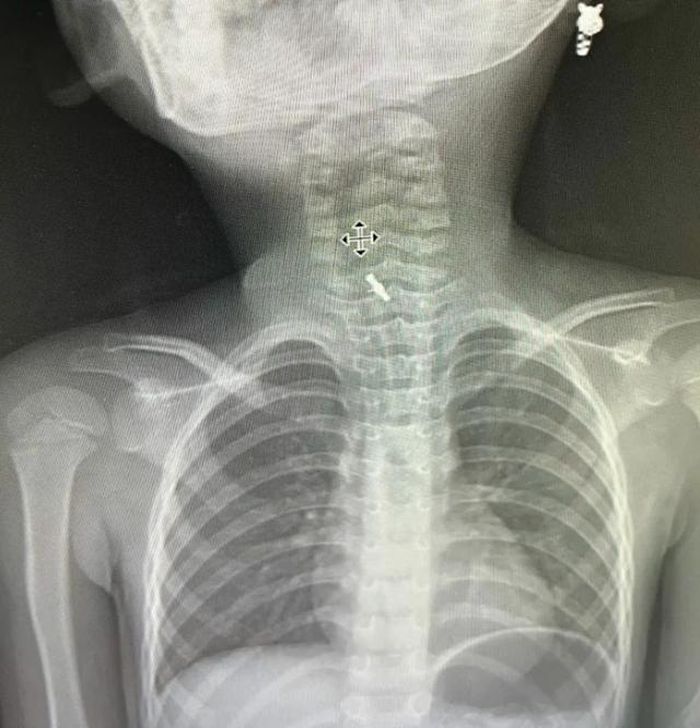

Hình ảnh chụp X-quang xác định dị vật mắc tại thực quản.

Tại viện sau khi thăm khám và chụp chiếu, hình ảnh chụp phim X-quang cho thấy bệnh nhi có dị vật mắc sâu trong thực quản. Các bác sĩ đã thực hiện nội soi bằng ống cứng và gắp dị vật ra ngoài.